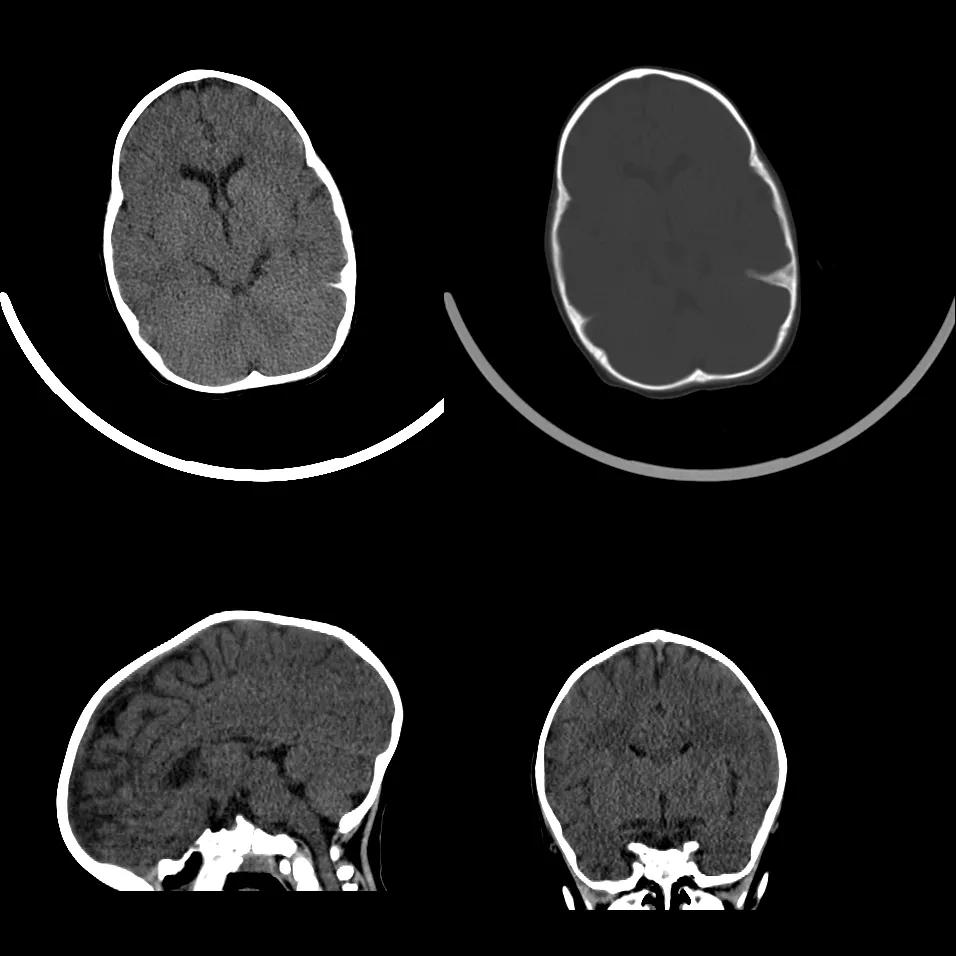

狭颅症

狭颅症(Craniosynostosis)亦称为颅缝早闭或颅缝骨化症,是一种少见的头颅先天性畸形,可有家族史,属于常染色体隐性遗传,机制不明确,可能是颅缝膜性组织内异位骨化中心生长的结果

由于一条或数条颅缝过早闭合,颅骨只能在其他方向代偿地生长,形成头颅畸形,颅腔容积的过早固定,限制了脑的正常发育,以至于产生头颅畸形、颅内压增高、智能发育障碍和眼部症状

依据受累颅缝不同,头颅畸形可有不同类型表现。最常见的是尖头畸形,是由于冠状缝加另一颅缝早期闭合所致,表现为头颅垂直径增加,前后径变短,额顶部倾向于垂直上升,使头颅变形呈塔状,前颅窝变短,眼球突出

矢状缝提早闭合形成长头畸形,又称舟状头,表现为头颅横径生长受限,而前后径生长显著,头长而窄,呈舟状,颅底下陷,矢状缝前部升高,枕部下陷

冠状缝早期闭合或伴人字缝早闭,形成短头畸形,主要表现为头颅前后径变短,垂直径和横径增加,颅后窝变短而深

狭颅症常见症状有: ①眼球突出,视力障碍及视野缺损,视乳头水肿或萎缩; ②智力障碍; ③癫痫; ④运动障碍; ⑤颅压增高; ⑥合并其他畸形

case 1:幼儿男性,1 岁 2 月,出生后发现头颅畸形 1 年余。

诊断:狭颅症。